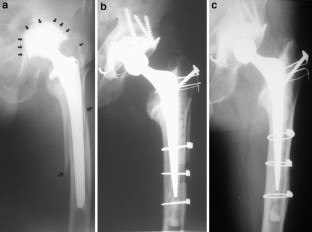

Fig. 1